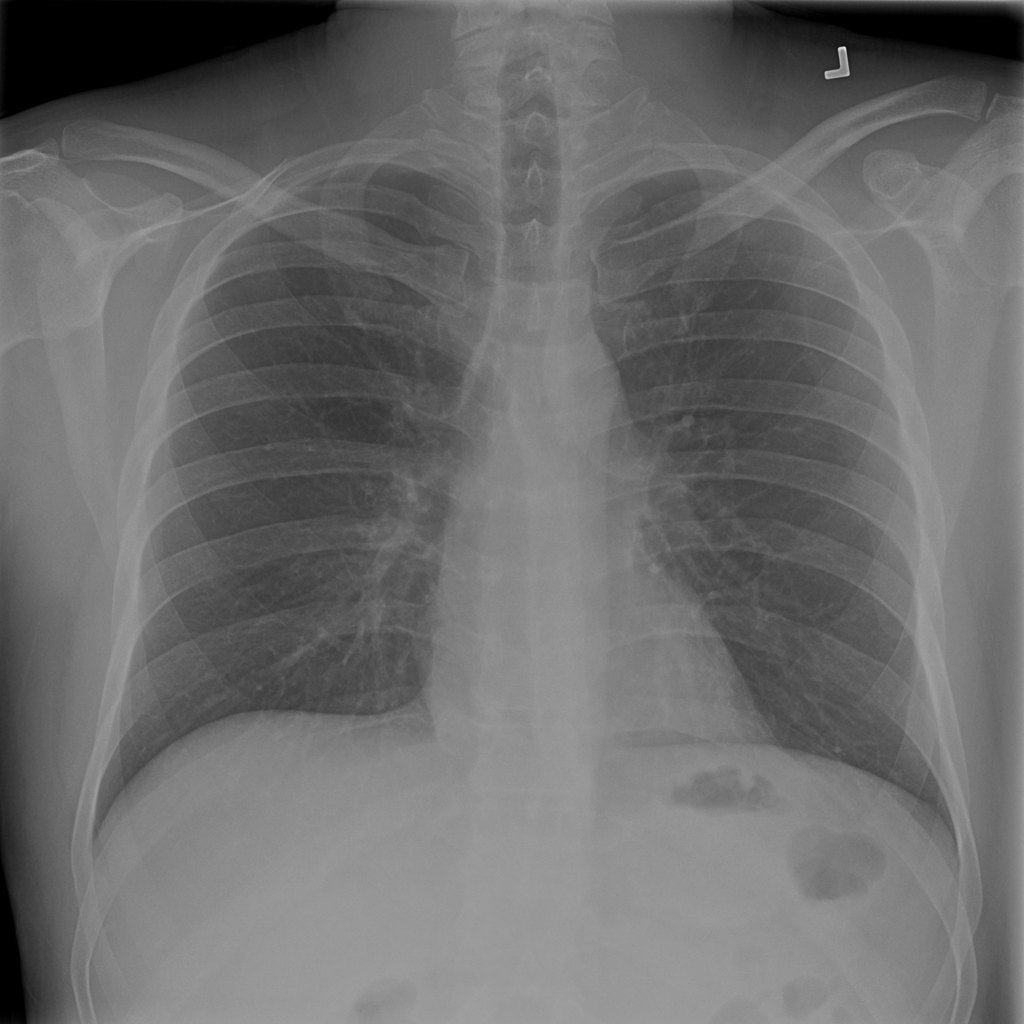

PAT-EBE1 · IMG-019Pneumonia

PAT-EBE1 · IMG-019

AP